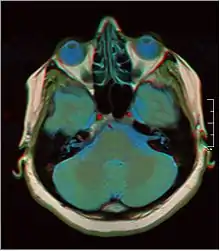

![]() Cross-sectional T1-weighted MRI of a healthy human brain acquired with an ultra high-field MR of 7 Tesla field strength | |

Brain regions on T1 MRI

T1 (note CSF is dark) with contrast (arrow pointing to meningioma of the falx)